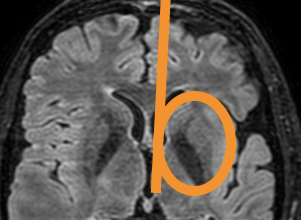

As a senior resident I reported an MRI of the brain of a patient with the cortex looking diffusely abnormal. There was a comparative scan, made 5 years earlier, briefly after the new 3T scanner had been set up in our hospital. This initial scan had been interpreted as normal by the professor in neuroradiology, a very knowledgeable doctor. Although the diffuse cortical abnormality was already visible, it was not recognised because inexperience with the 3T image.

Neuroradiology requires not only familiarity with the normal (MR) image but also understanding of the (patho)physiology. Whenever the physiology of the brain becomes too complicated for me, I go back in embryology to the neural tube, before the neurons and glial cells started to move and intertwine.

In Brain bit by bit vlogs I would like to share and show what I learned and know about different brain diseases, commenting on the radiological macroscopic picture and discussing what happened and happens at the microscopic, invisible cell level. Because this knowledge enables not only recognition of focal, obvious lesions in the brain but also diffuse, subtle disease that has just as much impact on life.